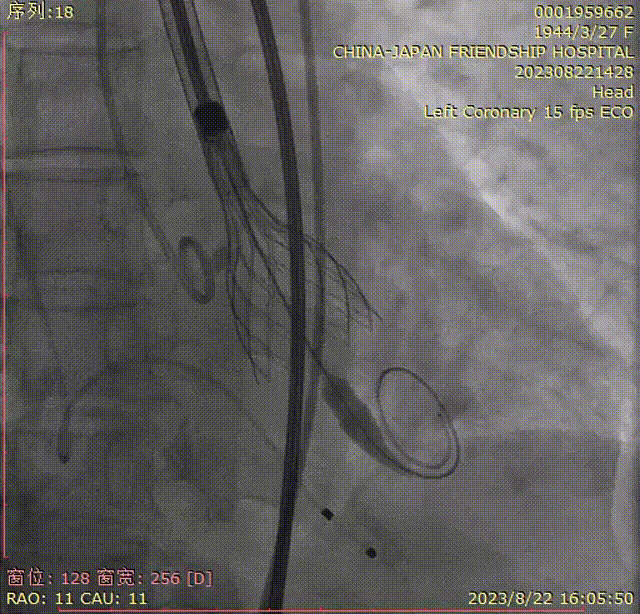

第四次定位和释放,右窦中心位,瓣上2mm释放;

根部造影评估,瓣架底边对齐,左冠显影良好,同轴性一般,瓣膜压缩,锚定良好,瓣下深度4-5mm;

瓣膜脱钩,完成释放,最终造影显示瓣膜形态佳,未见明显反流;

回撤脑保护装置,完成手术。